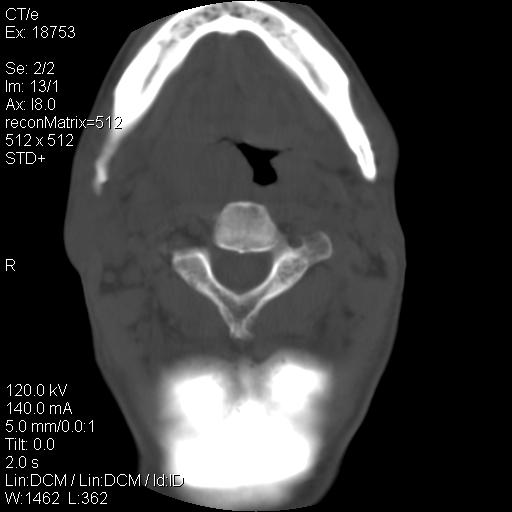

标题: CT21693:男 58岁 右侧咽部疼她2天余 PE:右侧扁桃体肿大 压痛 [打印本页]

标题: CT21693:男 58岁 右侧咽部疼她2天余 PE:右侧扁桃体肿大 压痛

右化脓性扁桃体炎症伴咽后壁脓肿形成.

1 弥漫性肿胀,与周围组织分界清晰,发病急,有明显症状,考虑急性炎症【wbc]

弥漫性肿胀,与周围组织分界不清,发病急,有明显症状,考虑:感染性病变!